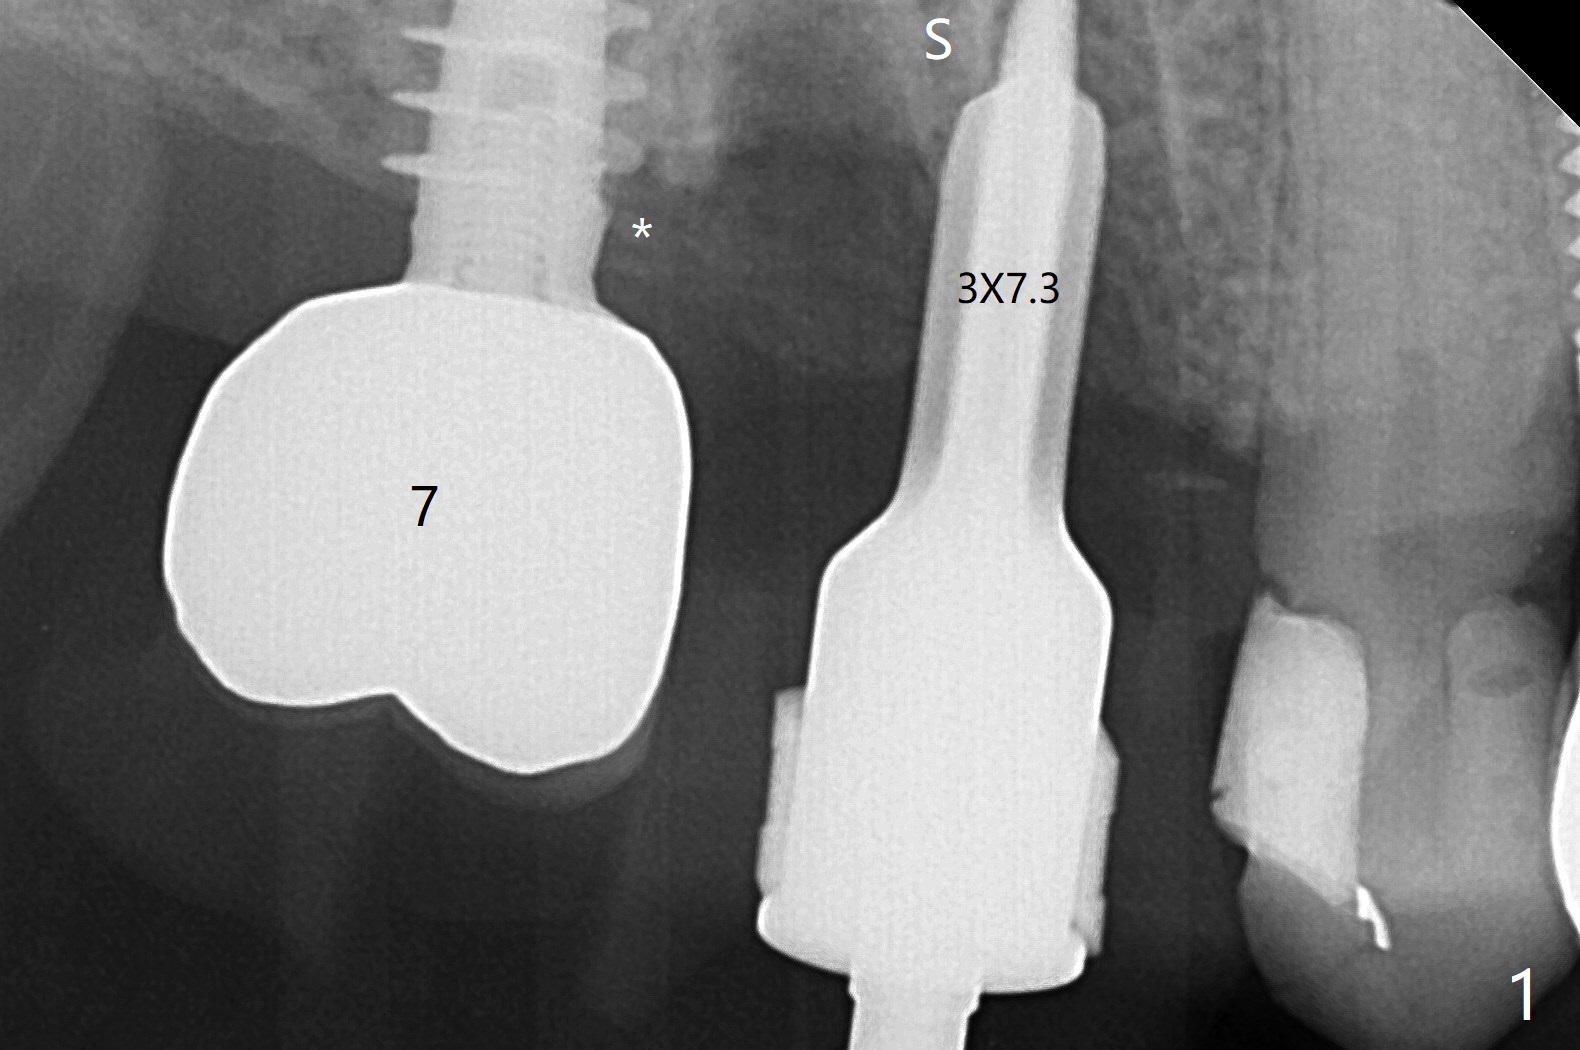

右上6拔牙困难,需要分根。3毫米补偿磨平钻头不能接触尖细中隔,即使使用外科手机和钻头,在导板指引下,尖钻头没有在中隔(S)打洞,使用2.2x7.3毫米钻头后,发现钻洞在近中颊侧窝。用过大一号钻头后,拍摄根尖片,方位偏差不大(图一,二),所以继续钻洞,钻头直径小0.5毫米,放置IS报废4.5乘10毫米植体,稳定性可以,也放置IS准基台(5.2x3毫米)。放置5x11(2)毫米Magicore(~20 Ncm),好像太接近近中牙槽骨(图三:*)。即刻放置4.3x3毫米实心基台。胶原塞放置远中颊侧和腭侧牙槽窝后,骨粉不仅覆盖刚植入的植体螺纹,而且推往7近中(图四:*(事先需要去除那里软组织,与图一比较))。其实可以先徒手用尖钻头在尖细中隔开始钻洞,为后来导板钻洞引导。